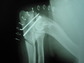

Cadera con artrosis severa. Deformidad de las cabezas femorales , normalmente esféricas, y múltiples osteofitos ( fragmentos óseos ) dañando el fémur y acetábulo ( flechas)

La artrosis es una enfermedad articular caracterizada por una degeneración y erosión del cartílago articular, y por la producción de hueso de nueva formación (osteofitos) en los márgenes articulares. Otros sinónimos son “osteoartrosis”, por estar también afectado el hueso subcondral, con esclerosis, inflamación y microfracturas, o “osteoartritis”, para hacer hincapie en la naturaleza ligeramente inflamatoria del proceso, sobre todo a nivel de la membrana